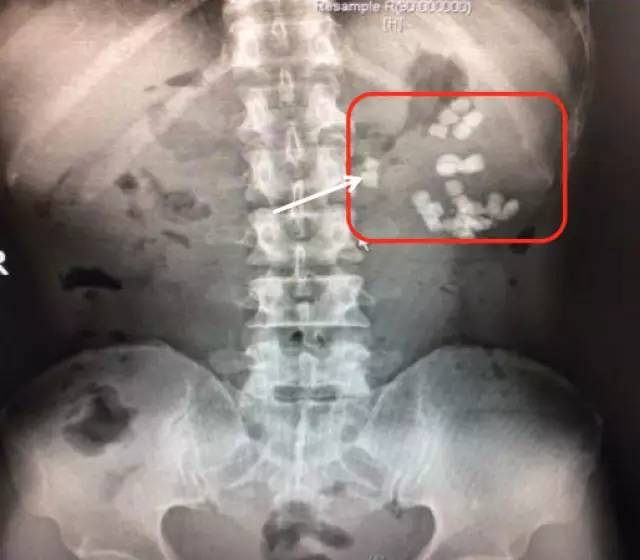

柯先生慕名来到我的门诊就诊。简单询问病情后,我给他开了KUB的检查单,KUB结果如下:

可见相当于左肾区(红框内)多发结节状密度增高影聚集,部分呈鹿角型。这是一个非常复杂的肾结石,虽然还没有做CT检查,但已可以判断这个肾脏功能一定受损严重,当时就建议柯先生住院微创手术治疗。

第一次来福建医科大学附属第一医院KUB检查结果

可见相当于左肾区(红框内)多发结节状密度增高影聚集,部分呈鹿角型